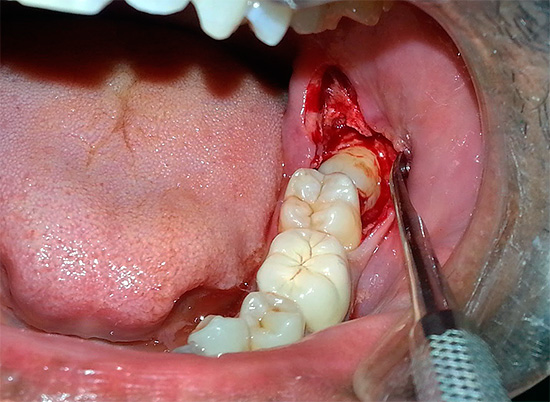

- Remoção do dente do siso retardado inferior (isto é, que não pode cortar adequadamente). Como regra, a operação para removê-lo é bastante traumática, durante a qual o médico disseca a gengiva e, às vezes, para um melhor acesso, expande bastante a ferida.Devido ao grande número de tecidos bem supridos de sangue, removendo o dente do siso inferior freqüentemente ocorre sangramento abundante e, com lesões significativas nos ossos e na gengiva, um inchaço na bochecha ocorre no primeiro dia após a remoção do dente "sábio".

Se a alveolite for diagnosticada, o dentista realiza anestesia de alta qualidade e realiza curetagem (purificação) do orifício a partir de um coágulo de sangue em decomposição e, às vezes, também a partir de restos não removidos anteriormente de partículas de um dente doente, granulomas, cistos, com a lavagem dos poços com soluções anti-sépticas. Se necessário, a ferida pode ser suturada. Depois disso, são prescritos medicamentos antibacterianos, na maioria das vezes para uso tópico na forma de lavagens ou pomadas.